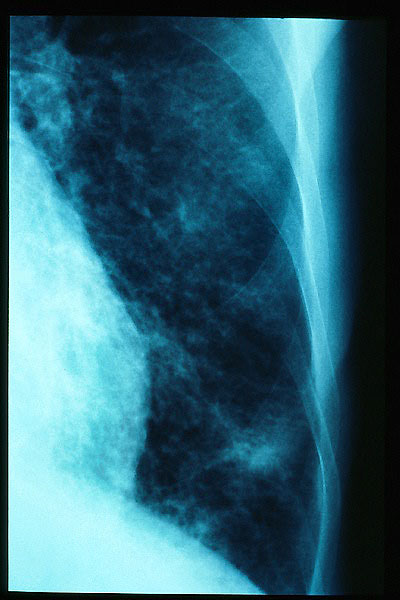

Condensación en base izquierda.